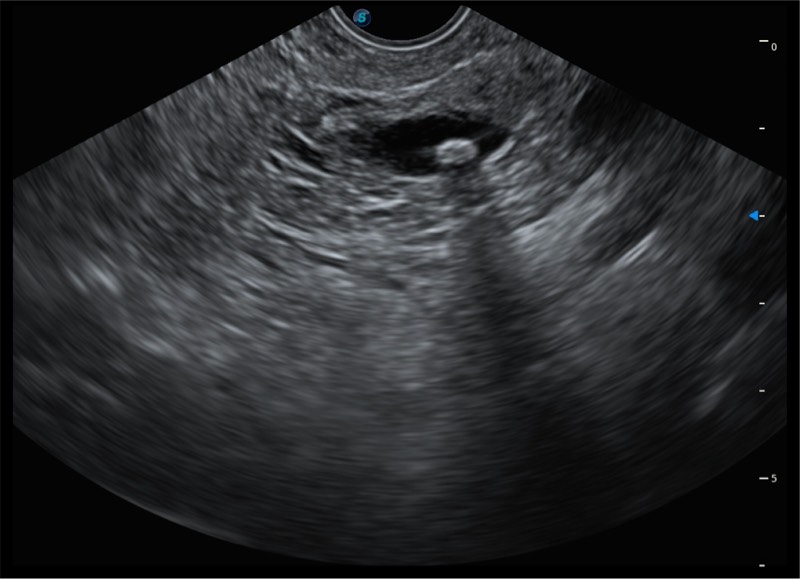

搭载百万级CMOS成像技术

及自主研发凸阵换能器,

可呈现优质的内镜和超声画面

基于二十年的超声技术积累,16877太阳集团提供了最新一代的独立超声主机,在提供高质量图像的同时满足多学科使用。具备常见多普勒技术并提供弹性成像、声学造影等高端影像技术。新一代传感器具有更强的抗干扰能力并减少图像伪影。